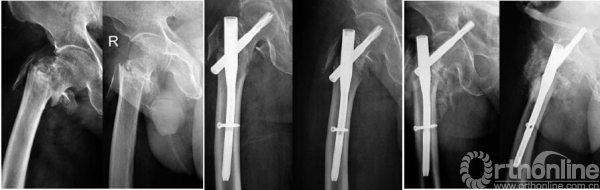

倒置LISS固定组56例骨折一期愈合(图1),愈合时间为3~12个月,平均3.8个月;其中3例发生骨折不愈合,4例骨折延迟愈合。髓内固定组246例骨折一期愈合,愈合时间为3~6个月,平均3.3个月;其中3例发生骨折不愈合,8例骨折延迟愈合。

图1 男,64岁,跌倒致股骨转子下骨折 A 术前三维CT重建示股骨转子下骨折,Seinsheimer 5型 B 选用LISS内固定治疗,术后2个月正侧位X线片示骨折对位良好,骨折线模糊 C 术后8个月正侧位X线片示骨折愈合良好